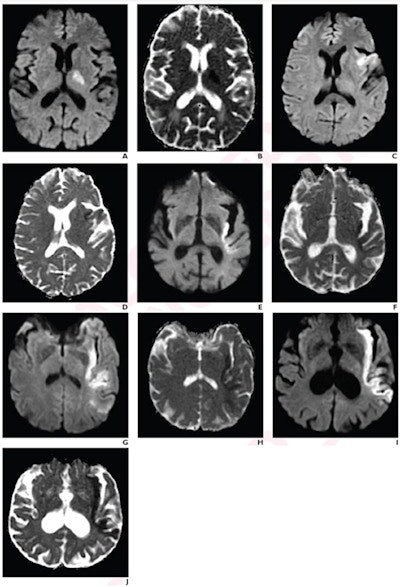

Images represent acute ischemic stroke patients with each PIRI score on a five-point scale. (A) Diffusion-weighted imaging (DWI) and (B) apparent diffusion coefficient (ADC) mapping show a 71-year-old patient with 0% insular ribbon infarction, score 0. (C) DWI and (D) ADC mapping show a 62-year-old patient with 25% insular ribbon infarction, score 1. (E) DWI and (F) ADC mapping show a 90-year-old with 50% insular ribbon infarction, score 2. (G) DWI and (H) ADC mapping show a 59-year-old with 75% insular ribbon infarction, score 3. (I) DWI and (J) ADC mapping show a 69-year-old with 100% insular ribbon infarction, score 4. Images courtesy of the American Roentgen Ray Society.In their research, Regenhardt and colleagues wanted to look at associations of PIRI with infarct growth rate during the initial 48 hours after presentation, as well as with 90-day outcomes, in patients with LVO stroke.